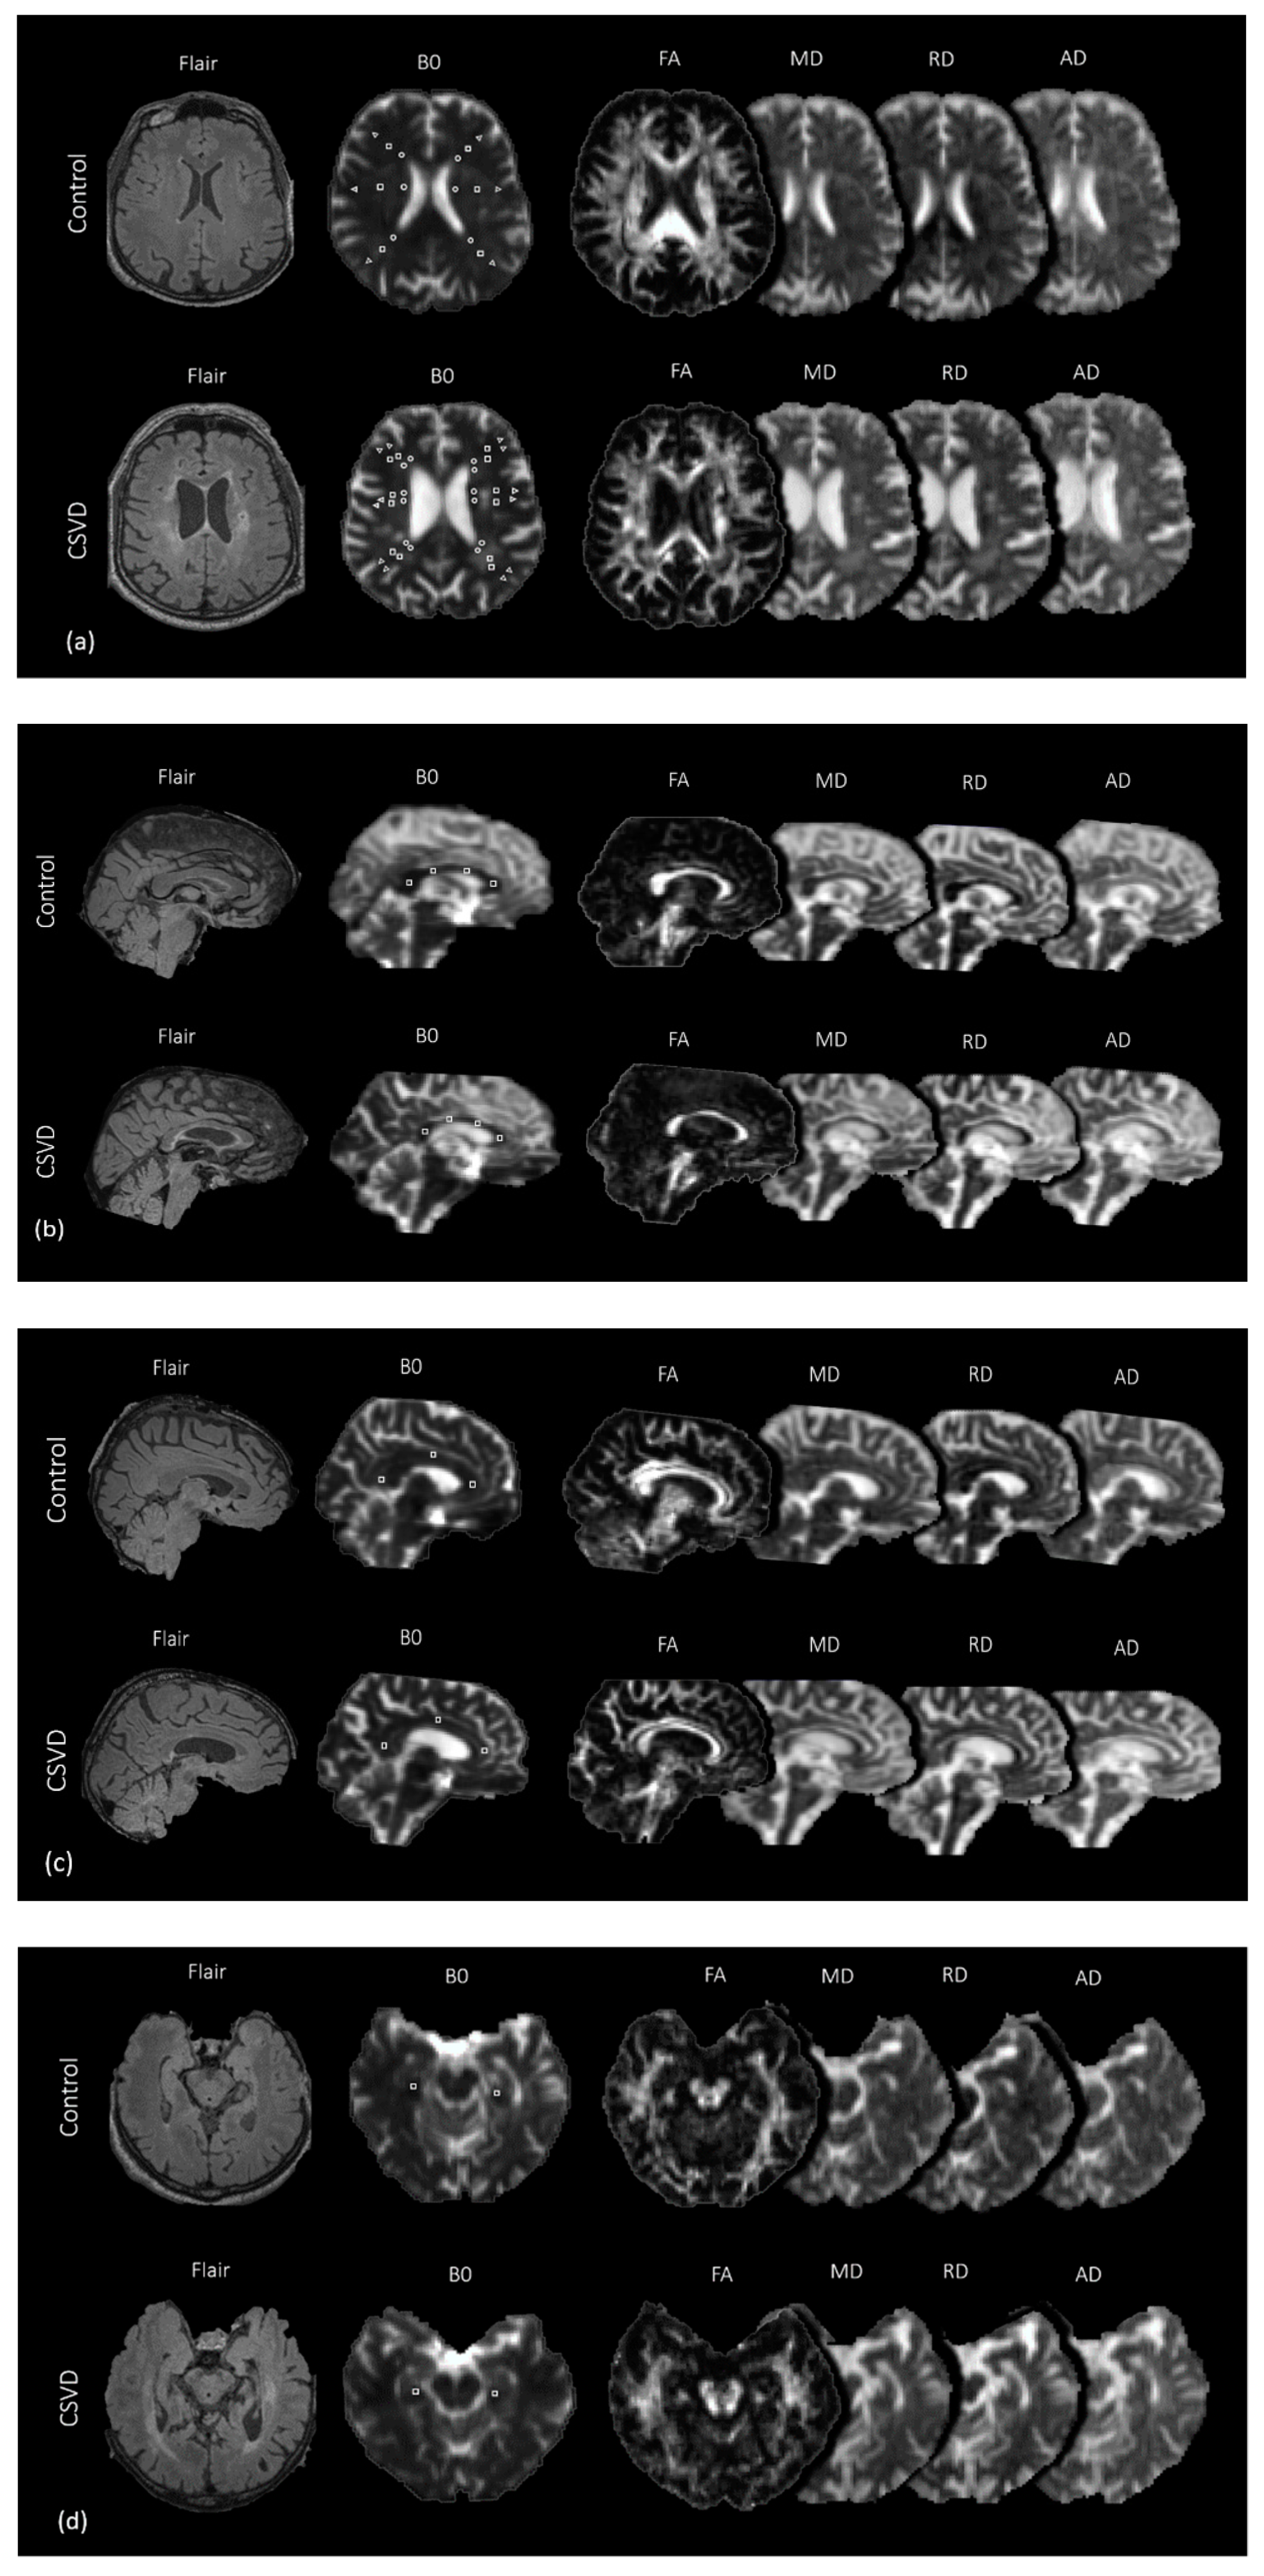

2. Materials and Methods

3. MRI Protocol and Imaging Analysis

3.2. Diffusion-Tensor Imaging